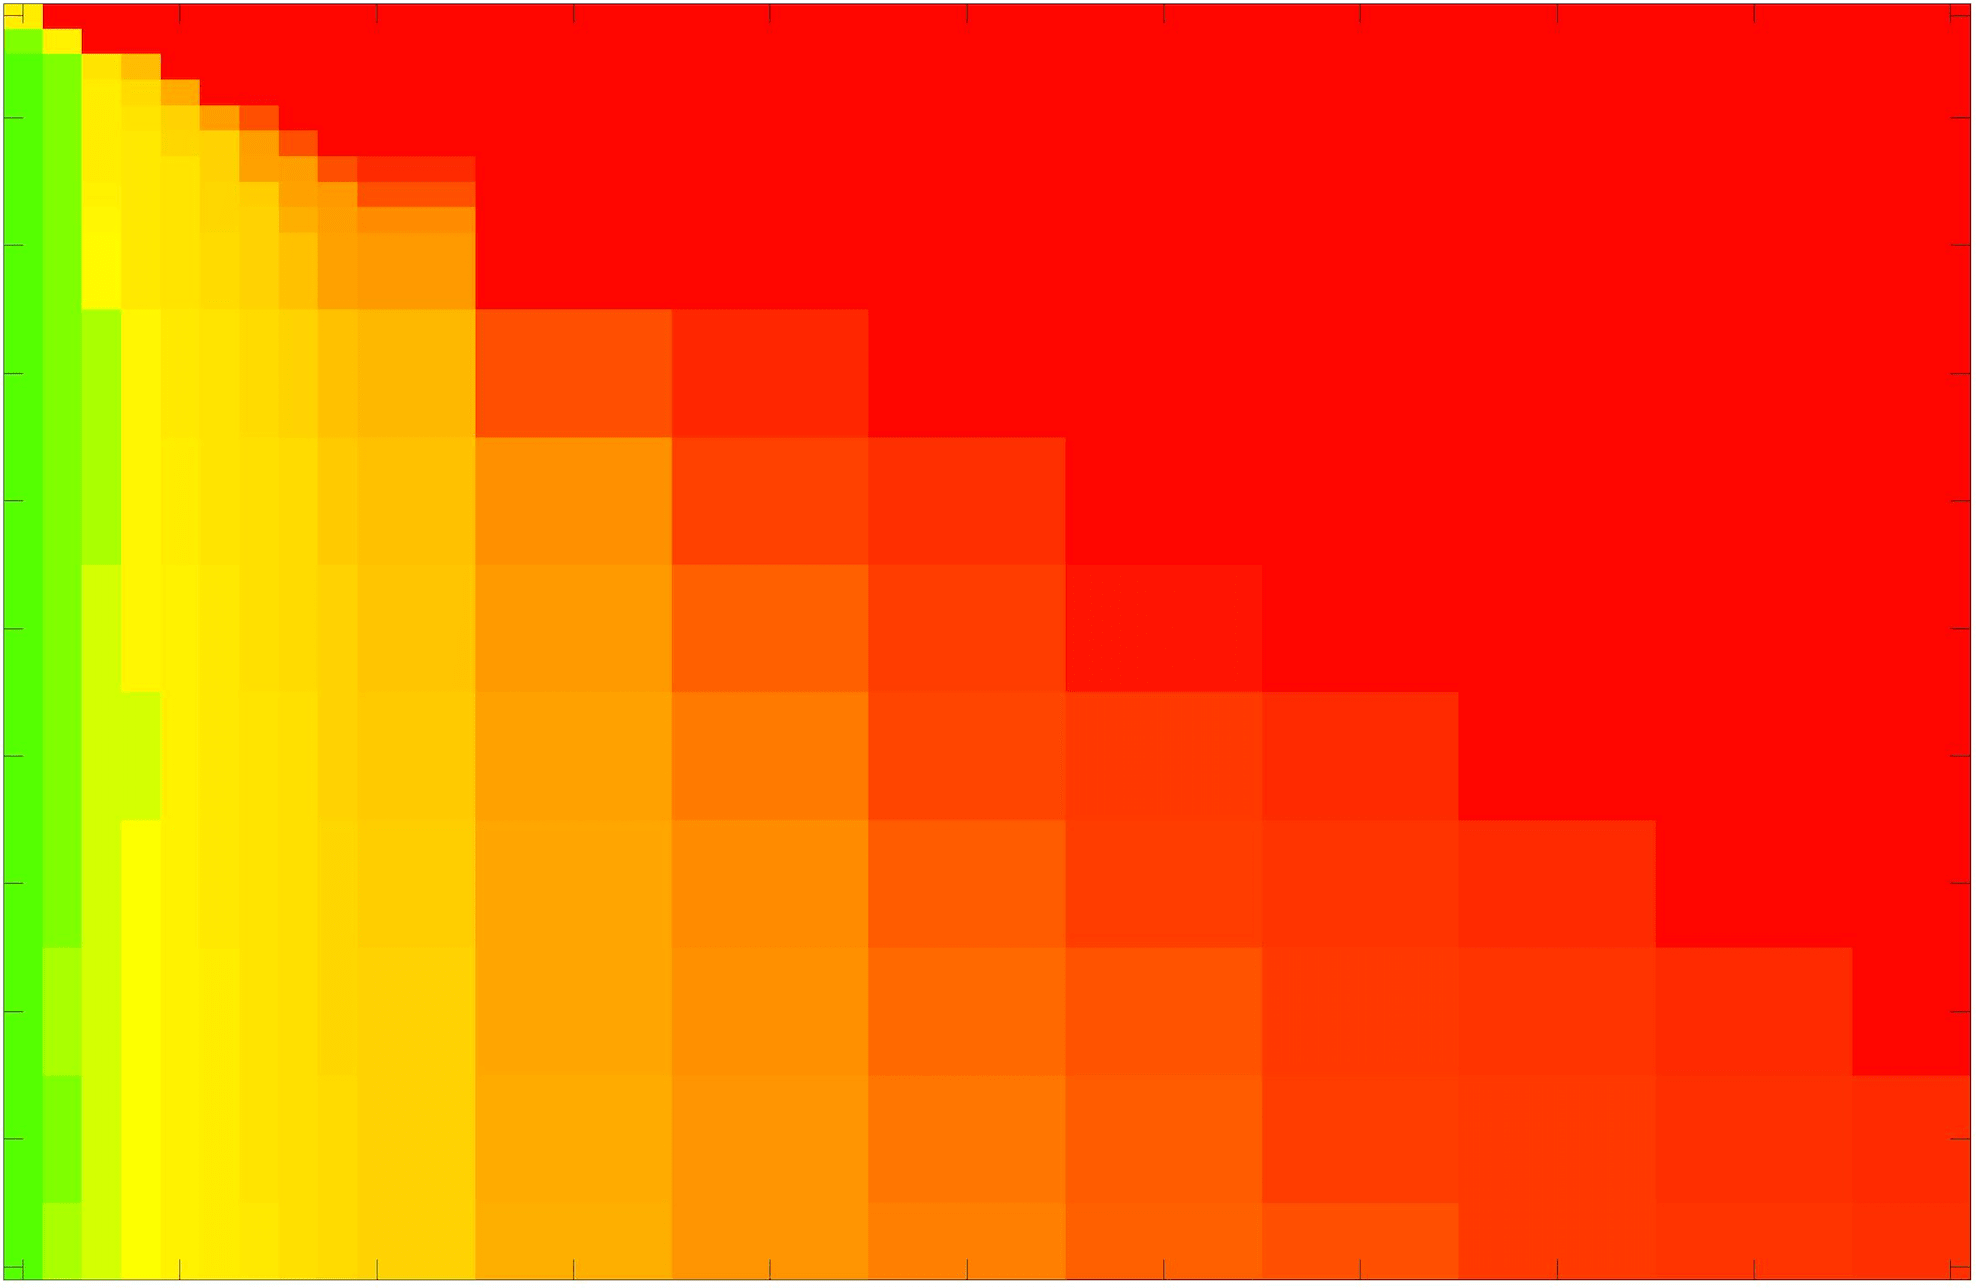

In these tests we aim to demonstrate how sensitive to parameter choices each choice of fitting term is. To accomplish this we perform the segmentations for each of the models discussed (CV, RSF, LCV, HYB, GAV) and the proposed model for a wide range of parameters and compute the TC value. The parameter range used is . Due to computational constraints, we run for each integer between 1 and 10, and every fifth from 15 to 50. This aspect of a model’s performance is vital when used in practice. The less sensitive to parameter choices a model is the more relevant it is in relation to potential applications. It should be noted that we neglect to test the selective models detailed in §3 with respect to parameter robustness as we are using the authors’ implementation of each approach. Instead, we make direct comparisons in the following sections.

The TC values for the parameter sets are presented as heatmaps in Figs. 11–13. A heatmap is a convenient way to display accuracy results for hundreds of tests concisely. In Fig. 9 we give an example heatmap with the same axes used for those in Figs. 11–13. For each of the combinations of parameter values we give the TC value of the segmentation result and represent it by the appropriate colour. The corresponding colour scale is shown in Fig. 8. Qualitatively, the more green areas of the heatmap the more accurate the model is for a wider set of parameters. Example results for Test Image 5 when varying (with ) for the proposed model are given in Fig. 10. Here it can be seen what each accuracy result corresponds to visually.

Synthetic Images. These results are presented in Fig. 11. For Test Images 1–2 we see poor parameter robustness from all competing models, except for GAV which performs reasonably well. However, the proposed model has minimal parameter sensitivity for these images, with good results achieved for almost every combination of values tested. For Test Image 3 all models have a reasonable parameter range (except for RSF), however the proposed model gives better quality results for a wider parameter range. The other models achieve reasonable results here as the foreground intensity of the ground truth is greater than the background , whereas for Test Images 1–2 they are equal . These results highlight the key advantage of the proposed model.

Real Images. In Fig 12 we present results for Test Images 4–6. Here, the proposed model performs in a similar way to its competitors because these images are more typical selective segmentation problems in the sense that there is a clear distinction between the foreground and background intensities. In particular, the values in each case are: Test Image 4 , Test Image 5 , and Test Image 6 . It can be seen that the proposed model is competitive compared to previous approaches. The performance is quite poor for Test Image 5, but is arguably still the best for this challenging case. In Fig. 13 we present results for Test Images 7–9. Here the proposed model outperforms previous approaches significantly for each image. This is mainly due to the type of image considered. Specifically, the true intensities are: Test Image 7 , Test Image 8 , and Test Image 9 . The proposed model is capable of achieving results where , with other models failing completely in these cases.